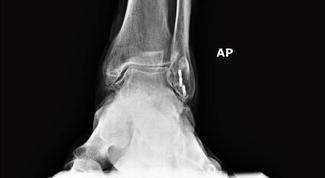

What makes it unique is its complete invisibility or radiolucency on x-ray. They do infuse a little bit of barium sulfate to be able to see the outline of the plate, but the plate is otherwise completely see-through, which makes it very convenient for the surgeon to be able to monitor their osteotomy or their arthrodesis site. And you can show your patients that and give them some confidence on their bone healing.